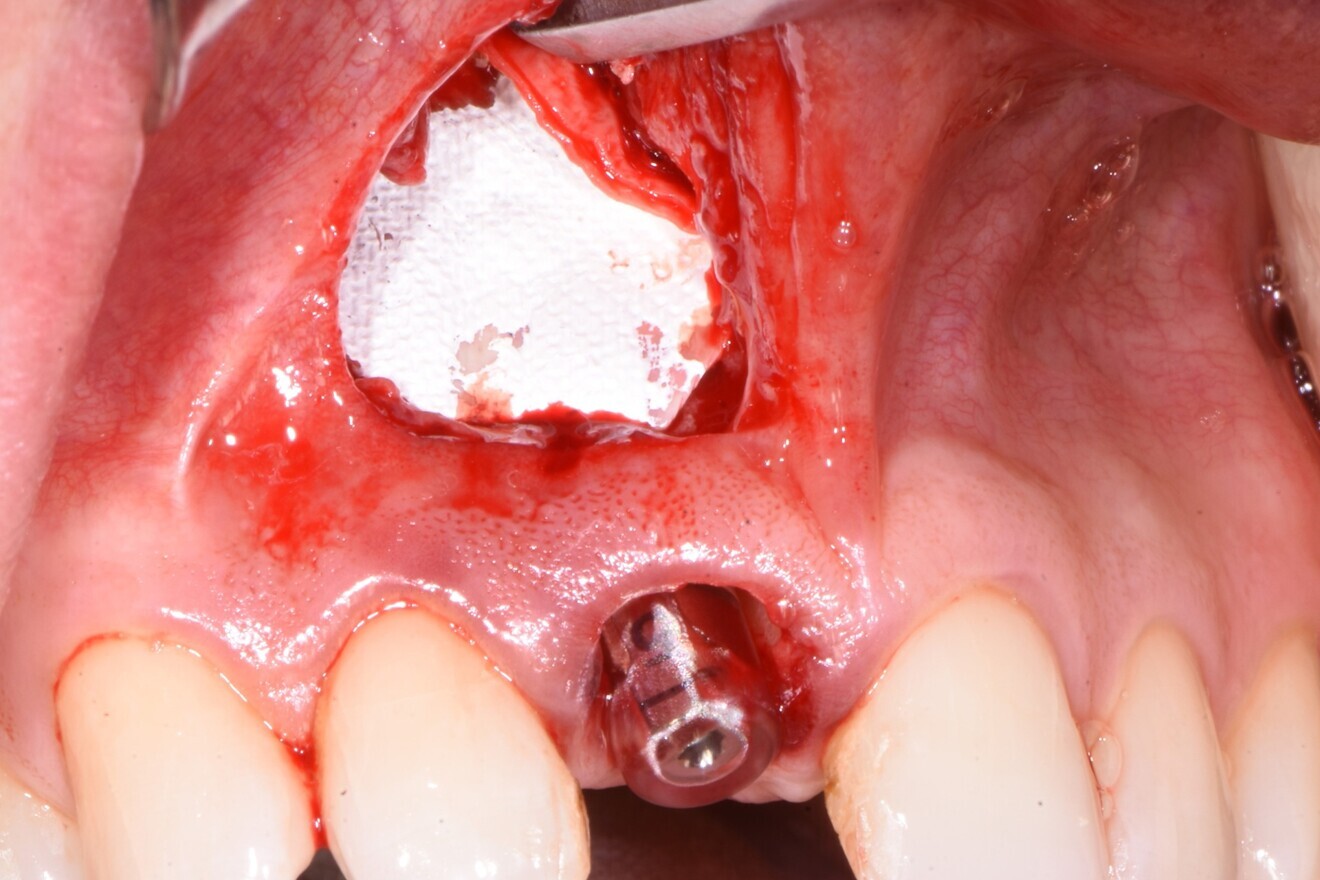

An atraumatic extraction protocol was used, involving initial luxation with a periotome and a rotational rather than facial-palatal method of displacement, thereby preserving the facial plate. Once the tooth had been extracted, a sub-sulcular envelope incision was used to gain access to the lesion, and the cyst was enucleated and the surrounding bone curetted and decontaminated (Fig. 5). A surgical guide was used to ensure the optimal position of the implant (Fig. 6), and the apical cutting threads of the PrimeTaper EV implant (Fig. 7) ensured that the implant engaged effectively with the apical bone, but the insertion torque only reached 20 Ncm owing to the large cyst-related cavity and the resulting lack of significant initial bone-to-implant contact. The baseline ISQ value was 61 and 65 in the facial-palatal and mesiodistal directions, respectively (Fig. 8), but in my experience, this combination of torque and ISQ value indicated that the implant was suitable for immediate loading, since the torque was ≥ 20 Ncm and the ISQ value was ≥ 65 in one direction.

Fig. 5: Extraction socket with the infra-bony cyst cavity exposed.

The infrabony defect was grafted with the bovine bone mineral and covered in a resorbable collagen membrane (OSSIX Plus, Dentsply Sirona) before the wound was closed and the immediate provisional restoration fabricated, which was under-contoured on purpose to allow for soft-tissue volume to increase around the neck of the crown and to bring the zenith coronally in order for it to be level with that of the adjacent central incisor (Figs. 9–11). RFA was then utilised to monitor changes in stability, increasing to 64/69 ISQ after six weeks and an impressive 79/82 ISQ after just over four months of healing. These values indicated progressive bone remodelling, graft consolidation and osseointegration and thus that the site was ready for definitive restoration.